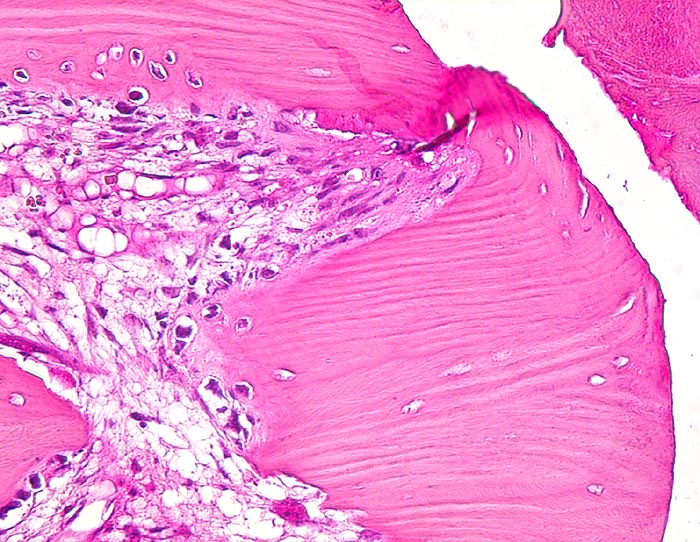

sekundäre Frakturheilung: Frakturspalt mit Kallus

Knochen, Rippe

Frakturspalt mit Fibrin. Devitalisierter ortsständiger Knochen mit leeren Osteozytenhöhlen begrenzt den Frakturspalt. Osteoklasten bauen das devitalisierte Gewebe ab. Granulationsgewebe im Markraum.

Konservativ behandelte Rippenfraktur nach Sturz vor einem Monat.

Histologie

160